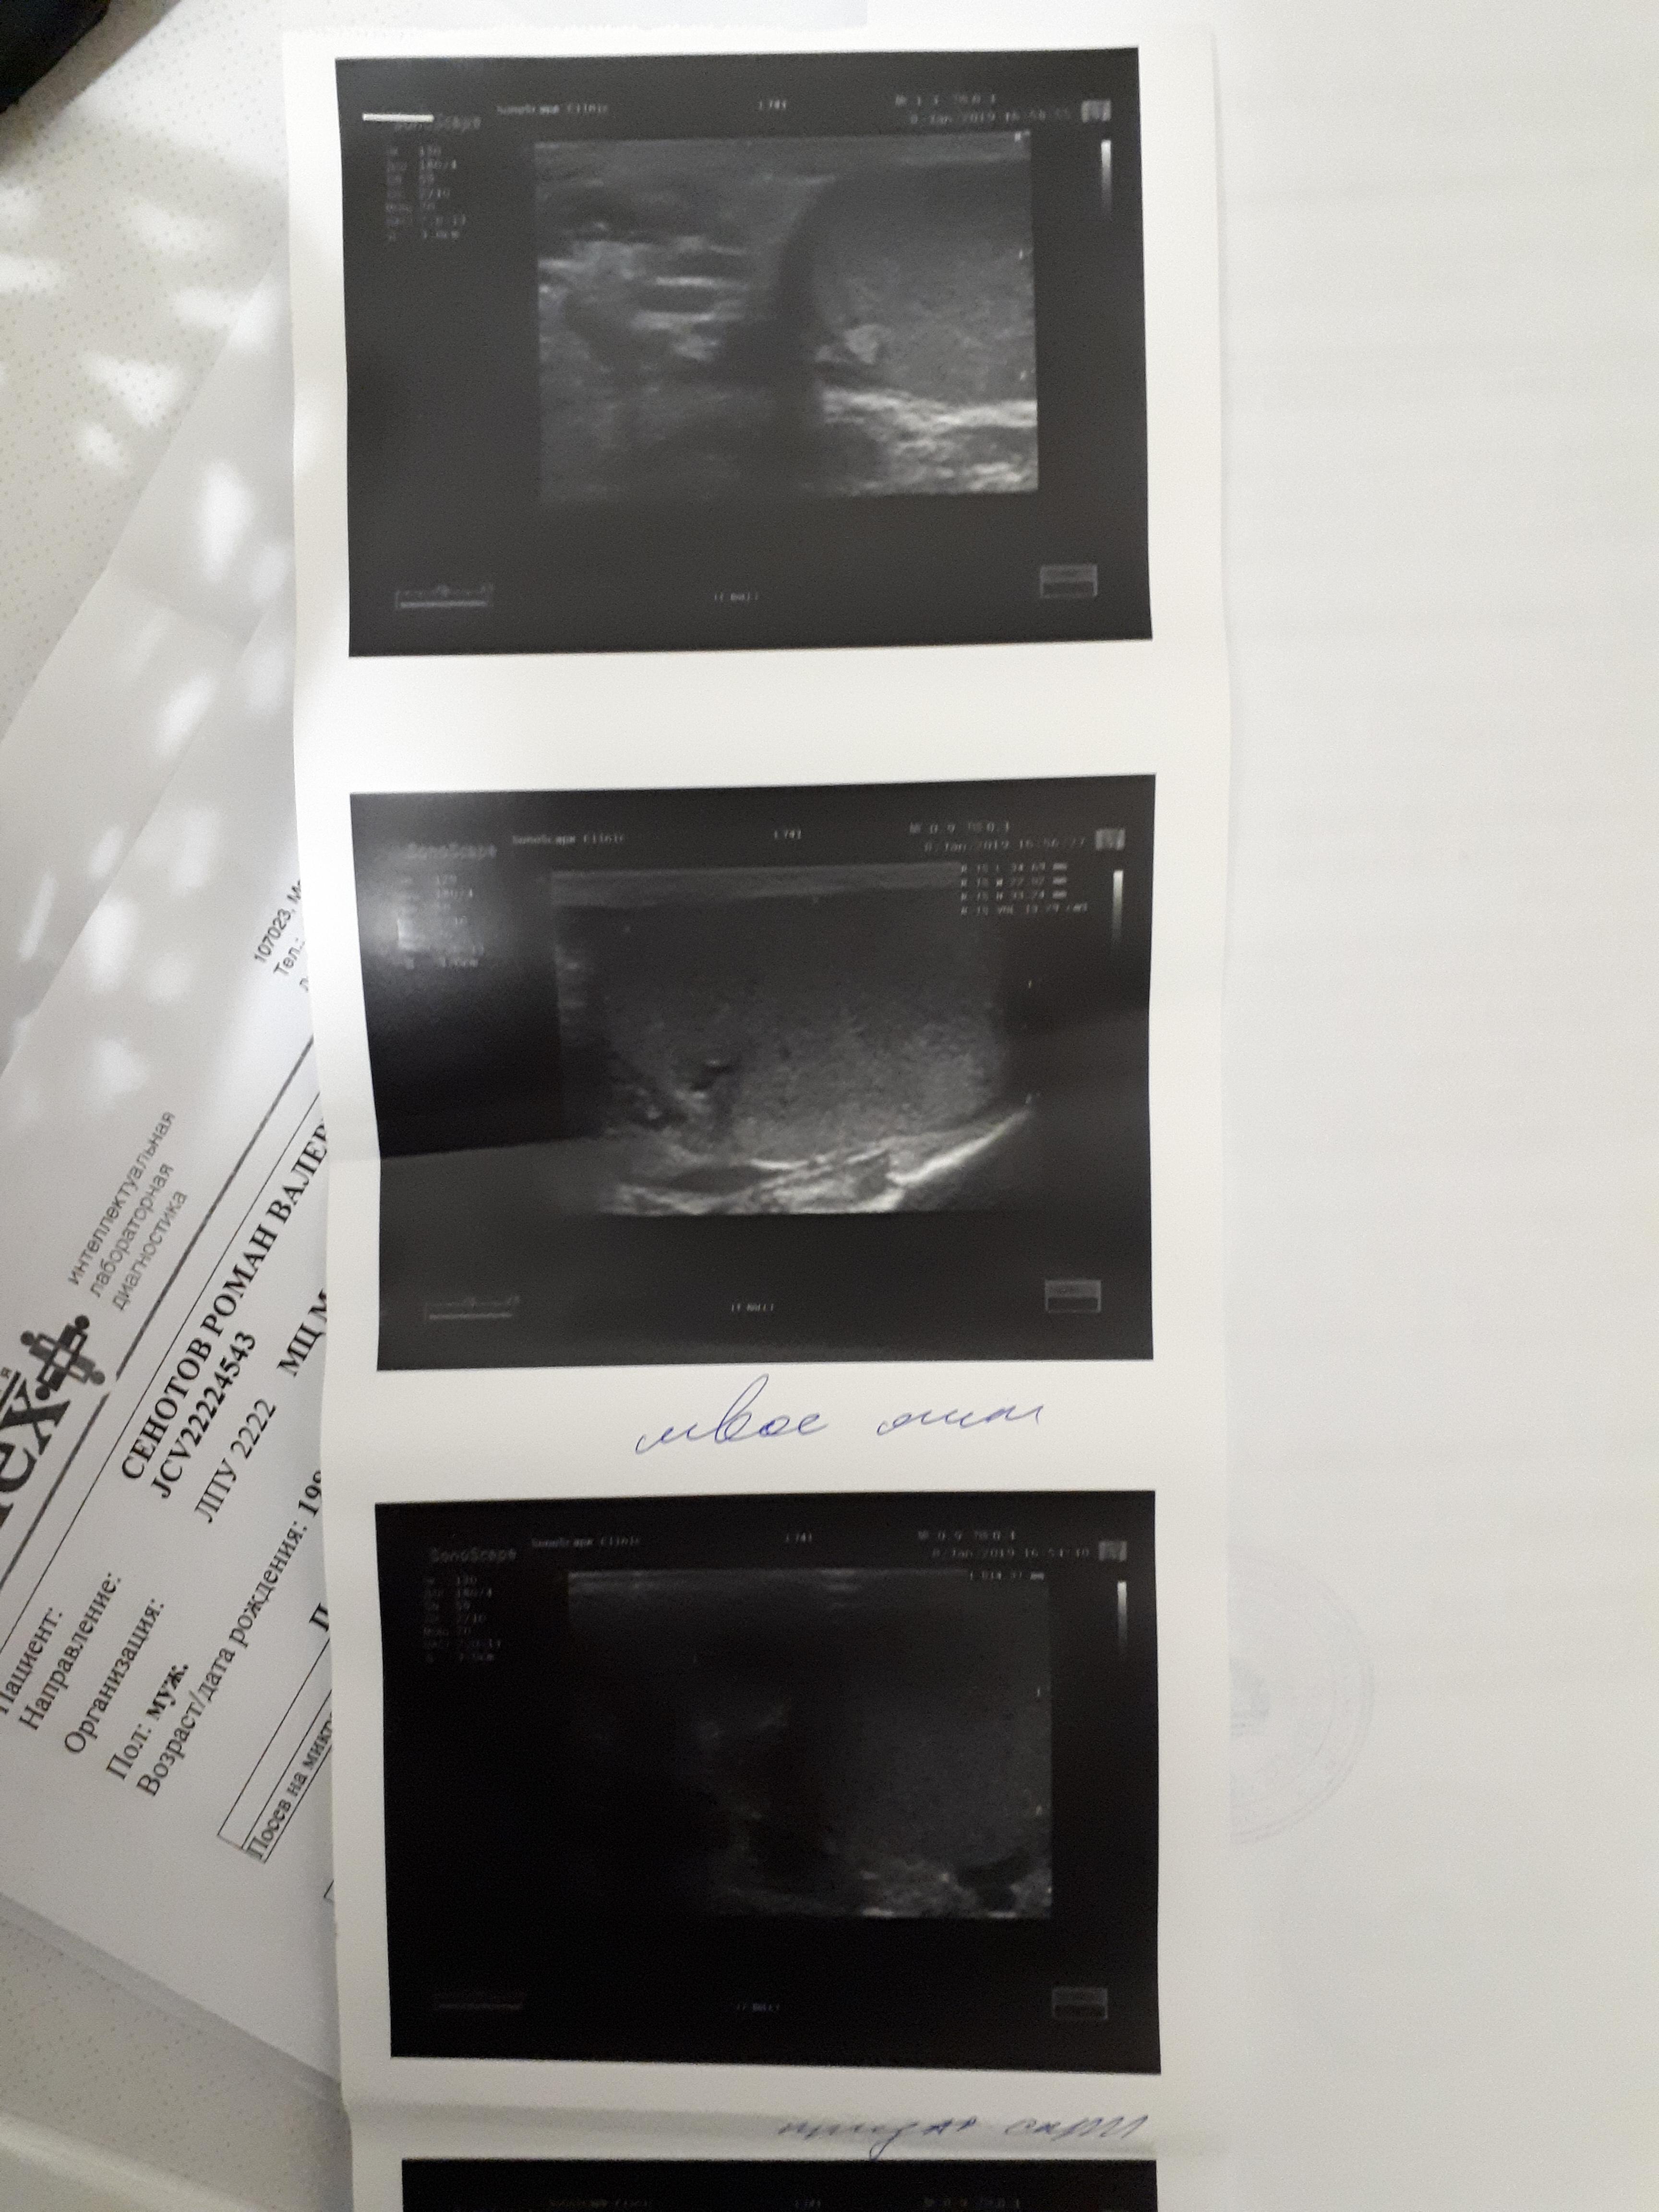

Здравствуйте ! месяц назад почувствовал резкую боль в правом боку, было подозрение на аппендицит (не подтвердилось) вместе с этой болью заболело правое яичко. Обратился к врачу сделал обследование пролечился не помогло боли остались. Обратился к другому урологу, он провел обследование назначил лечение. Вопрос правильный ли диагноз и назначенное лечение? (все обследования на фото)